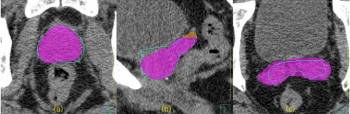

論文「Dosimetric Impact of Artificial Intelligence (AI)‑Based Autocontouring Software, OncoStudio, in High‑Risk Prostate Cancer Treatment Planning: A Three‑Group Comparative Study on the Slice Ranges of Seminal Vesicles」が発表されました。本研究では、OncoStudioによる高リスク前立腺がん患者の精嚢に対するAI自動輪郭抽出とマニュアル輪郭抽出との違いを線量で比較しています。CTV, PTVに対して、統計的に有意な線量差は認められず、処方に対する差は1%未満であることが示されました。この結果は、AI自動輪郭抽出が高リスク前立腺癌放射線治療計画において信頼性の高い選択肢であることを示唆しています。